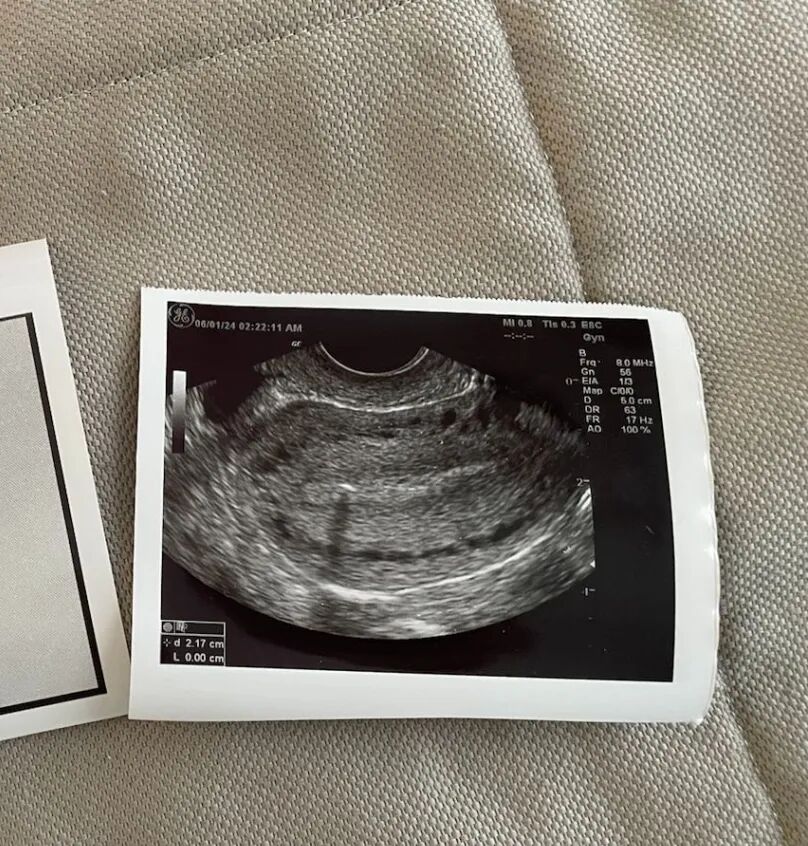

今天一早就收到了两位爱妈的喜讯!首先是爱妈K的好消息:在经历了一次因子宫内膜厚度不足而不得不取消的移植周期之后,她的准父母终于迎来了期待已久的佳音。在医生的精心调整下,第二轮准备移植两颗胚胎提高成功率,经过12天紧张的等待后,爱妈K的第二次移植成功,首次B超检查显示,HCG水平顺利翻倍,确认宝宝已成功着床,这对准父母来说无疑是一大喜讯。

在孕早期过程中,爱妈会在胚胎移植后的第十二天进行首次孕检,使用验孕棒来检测是否怀孕。验孕棒通过检测尿液中的人绒毛膜促性腺激素(HCG)来确定怀孕状态。接下来的两天后,将进行第二次孕检,以监测HCG水平是否翻倍。HCG水平的翻倍是孕早期胚胎发育良好的重要指标,如果水平成功翻倍,则表明怀孕进展稳定。